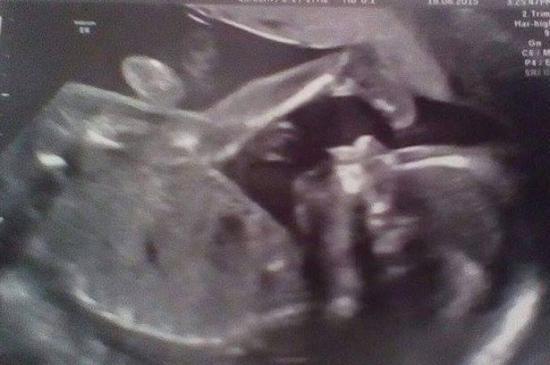

Femeia a descoperit că ceva este în neregulă cu fiul ei când acesta avea 20 de săptămâni. Medicii au observat că un ţesut moale neaşteptat creşte pe faţa lui. În urma analizelor, aceştia au confirmat că micuţul suferă de o rară boală, un defect care îi provoacă ca creierul să crească printr-o gaură din craniu.

Foto: dailymail.co.uk